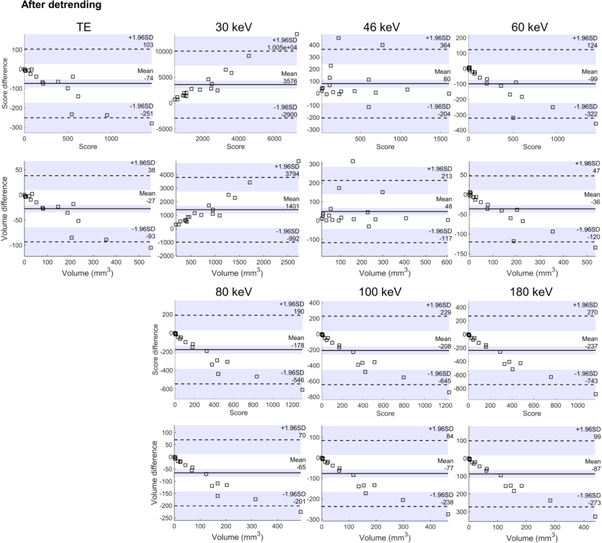

Strong correlations of both calcium score and volume between reference measurement (TE measurement of the rod) and TE measurement of the torso were found (table 2). The 46 keV VMI had the best overall correspondence with the reference method (BA slope values and correlation). The BA plots (figure 6) and slope analysis in table 2 showed that with the TE images, both the volumes and scores had a decreasing linear trend with volumes and correlations. This showed that calcifications with high volumes were underestimated in detruncated reconstructions. With the 46 keV virtual monoenergy, this trend was eliminated (figure 6).

Figure 6. Bland-Altman plots for the Agatston score and volumes for total energy images (TE) and virtual monoenergies. Detrended data is visualized.